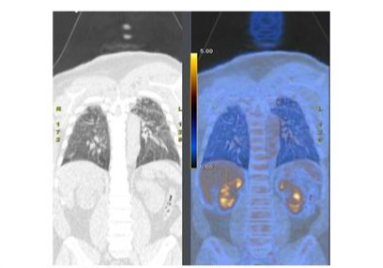

In patients with tuberculosis, ¹⁸F-FDG is useful for identifying both pulmonary and extrapulmonary disease, measuring disease activity, identifying individuals with latent tuberculosis infection at risk of developing active infection, and monitoring response to treatment⁷². Lesion activity correlates with disease activity. Using dual time-point imaging at one and two hours, it may be possible to distinguish active from inactive disease⁷³. Even when radiological features may remain unchanged, early treatment response can be assessed with ¹⁸F-FDG, significantly affecting patient management. In one investigation, ¹⁸F-FDG PET/CT performed after two months of treatment, was the best method for early prediction of treatment results and long-term outcome⁷⁴.